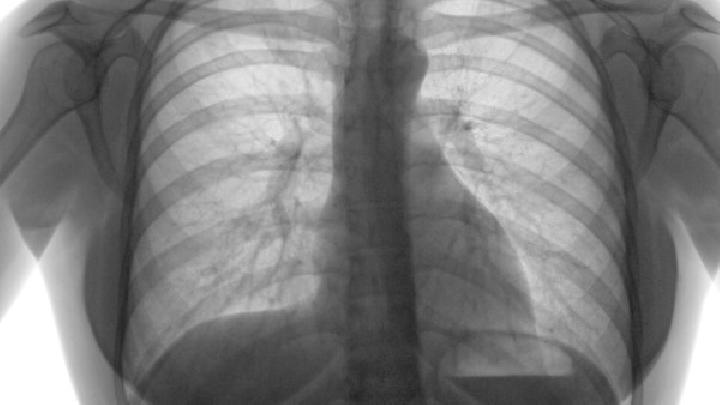

肺心病是属于典型的慢性复杂呼吸道疾病,发病机制不仅是单一的靶点改变,而是多个分子靶点失衡造成的,单纯对症治疗是无法彻底治愈疾病的。随着医学对人体细胞研究发现:人体中存在促纤维化细胞因子和抑纤维化细胞因子。当促纤维化细胞因子的活力和数量大于抑纤维化细胞因子时,肺器官纤维化就会出现;两种细胞因子达到平衡时,健康的人就没有肺器官组织纤维化之忧。

肺纤维化,即肺脏间质组织由胶原蛋白、弹性素及蛋白醣类构成,当纤维母细胞受到化学性或物理性伤害时,会分泌胶原蛋白进行肺间质组织的修补,进而造成肺脏纤维化;即肺脏受到伤害后,人体修复产生的结果,目前肺纤维化手术主要有微创手术和换肺手术两种。

在疾病进行救治之前,我们是不能逾越疾病的检查诊断,毕竟有效治愈病症的前提条件是将疾病诊断正确,肺纤维化这种威胁患者生命的疾病,我们必须做好它的检查诊断,那么肺纤维化的诊断标准有哪些呢?下面就此问题做一个详细的讲述。